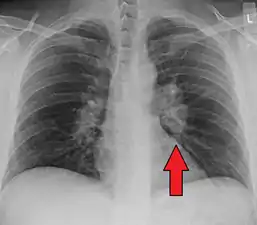

Chest X-ray showing the typical nodularity of sarcoidosis, predominantly in the hila of the lungs.